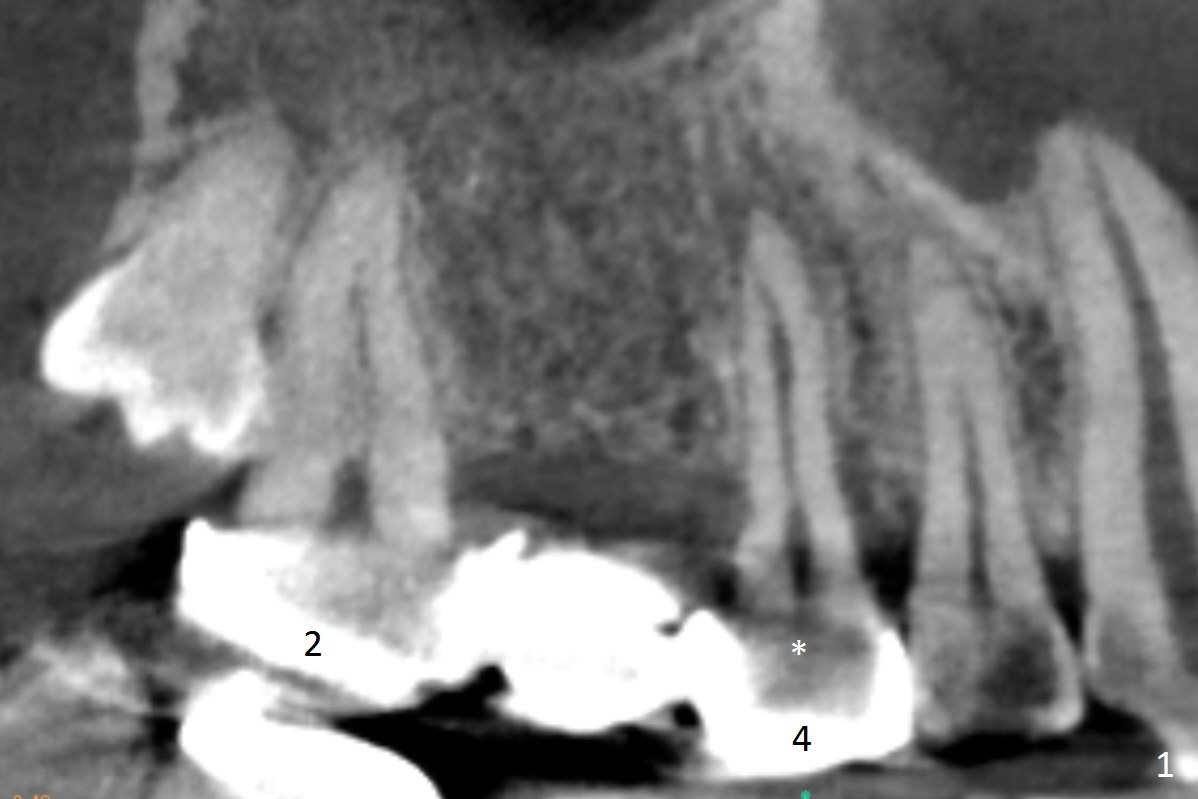

After implant at #19 and RCT at #14, the 36-year-old woman has discomfort in the upper right quadrant due to caries at #4 (Fig.1 *). After sectioning the bridge between #2 and 3, the retainer at #4 should be separated from the abutment by itself because of severe caries. Also examine the salvageability of #2. If the tooth #4 is nonsalvageable (Clindamycin), two implants will be placed at #3 and 4 (Fig.2-4). Since the ridge at #3 is wide (Fig.3, coronal section (B; buccal)), use Magic Split to start osteotomy, followed by Magic Expanders. The initial depth at #3 will be 12 mm and gradually increase to 14 mm. On the other hand, the bone density is higher at #4, drills will be used for osteotomy. Speed will be reduced at 50 RPM when the drills are more than 3.8 mm. Take intraop PAs as early as possible for trajectory confirmation.